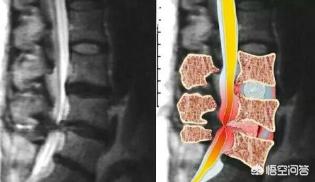

腰椎椎間板ヘルニアの病態は、腰椎椎間板(髄核、線維輪、軟骨板で構成)の変性によるもので、線維輪が部分的または完全に破裂し、髄核が突出して神経根や馬尾を刺激・圧迫する症候群であり、脊椎の変性疾患として臨床上よく見られる疾患です。主に腰痛、坐骨神経痛、下肢のしびれ、馬尾症候群などの症状が現れます。

腰椎椎間板ヘルニアによる坐骨神経痛の症状は、腰椎椎間板ヘルニアが神経根を圧迫した結果起こる腰椎3仙骨1椎間板病変に最も多く関連しています。

腰椎椎間板ヘルニアによる坐骨神経痛は、主に圧迫された側の神経症状です。そして、その症状は坐骨神経支配領域に顕著に現れます。

椎間板は2つの椎骨をつなぐ繊維状の構造で、周辺部の繊維輪と中心部の髄核からなり、水分を豊富に含んでいる。椎間板の変性、不良姿勢、長時間の座りっぱなしや立ちっぱなし、寒さ、冷たさ、湿気などにより、椎間板の末梢の線維輪が損傷し、椎間板の中心にある髄核が突出して神経根を圧迫する。臨床症状腰痛、下肢の放散痛やしびれ、下肢の筋萎縮が長期的にみられることがある。馬尾神経が突出部によって圧迫されると、二次排便の機能障害や会陰部のしびれとして現れる。